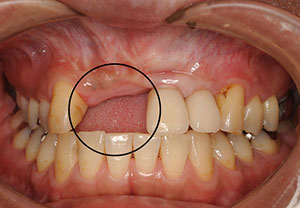

【症例1 57歳 女性 上顎前歯の違和感】

| 治療内容 | 主訴:上顎の前歯部分が疼痛により当院へ相談しに来院されました。 処置:骨が欠損していた難症例でしたので、帆年再生療法(GBR)と歯肉移植を併用したインプラント治療を行いました。十分な骨の再生が得られ、きれいな歯が入ったと喜ばれました。 |

| 費用 | 総額 962,500円(税込) ・インプラント様(片顎)CT撮影 11,000円(税込) ・静脈内鎮静法B(ドルミカム) 27,500円(税込) ・GBR(組織再生誘導療法)B(ソーセージテクニック) 154,000円(税込) ・フェクスチャー(インプラント) 242,000円×2本=484,000円(税込) ・セラミック冠(冠+アパットメント) 143,000円×2本=286,000円(税込) |

| 治療期間・回数 | 治療期間約2年 治療回数約30回 |

| リスク・デメリット | 外科手術が必要となりますので、神経の圧迫や損傷による麻痺や血管による出血、術後の腫れなどが生じます。時間と経過とともに自然にひいてきます。もし痛みがある場合は、鎮痛剤などの処方を行います。また、なるべく低侵襲な治療法を選択する事で負担の少ない治療を行います。そして神経損傷などのリスクを回避するために当院では、CT撮影による精密診断や神経や血管の位置をより正確に把握し、治療計画を立てて行います。 |